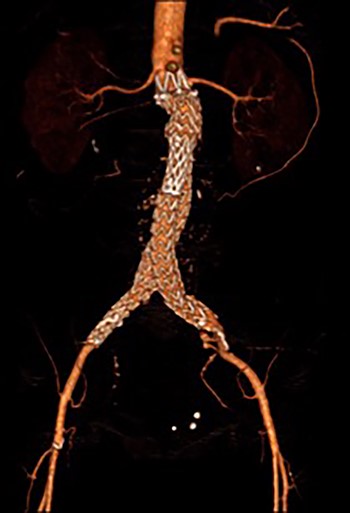

Post-lysis CT scanning showing fully re-canalized aorto-iliac system.

The patient was transferred to the high-dependency unit for observation during the thrombolysis. After 4-h, the patient was taken back to Interventional Radiology department for a check angiogram (Fig. 3). This demonstrated a fully re-canalized aorto-iliac system with no distal thrombotic or embolic complications. The thrombolysis infusion was stopped at this stage. In the post-operative period, anticoagulation has been continued with Apixaban. A CT scan 6 weeks post-procedure has confirmed ongoing patency of the endograft with no visible thrombus (Fig. 4).